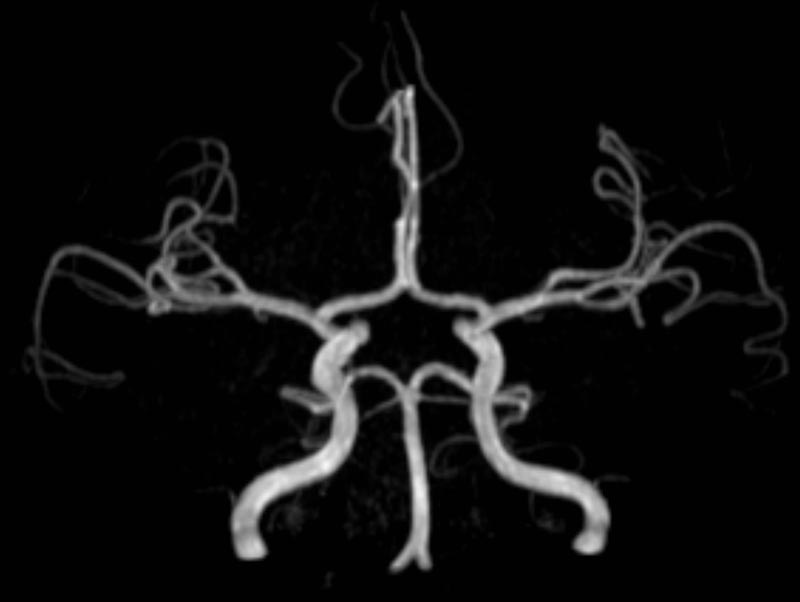

Kopf/Hals

• akute Schlaganfalldiagnostik und chronische Durchblutungsstörungen

• intrakranielle Gefäße (Abklärung Verschluss, Stenose, Aneurysma)

• Halsgefäße zur Therapieplanung (z.B. Stent, Operation)

MR-Angiografie (MRA)

• MR-Angiographie mit Kontrastmittel

• Erfassung arterieller und venöser Gefäße/Bypässe aller Körperregionen mit 3D-Rekonstruktion